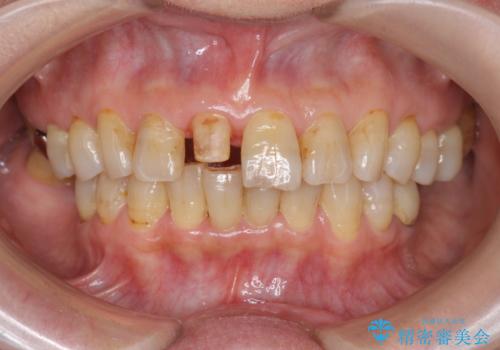

- 前歯を転倒で受傷し、審美性の回復を求めて来院されました。

近医で暫間的なコンポジットレジン修復が為されていましたが、色調に不満があるということでした。

色調の変化が少なく、長期的な予後を見込めるジルコニアクラウンで天然歯を模した審美性の回復を計画します。